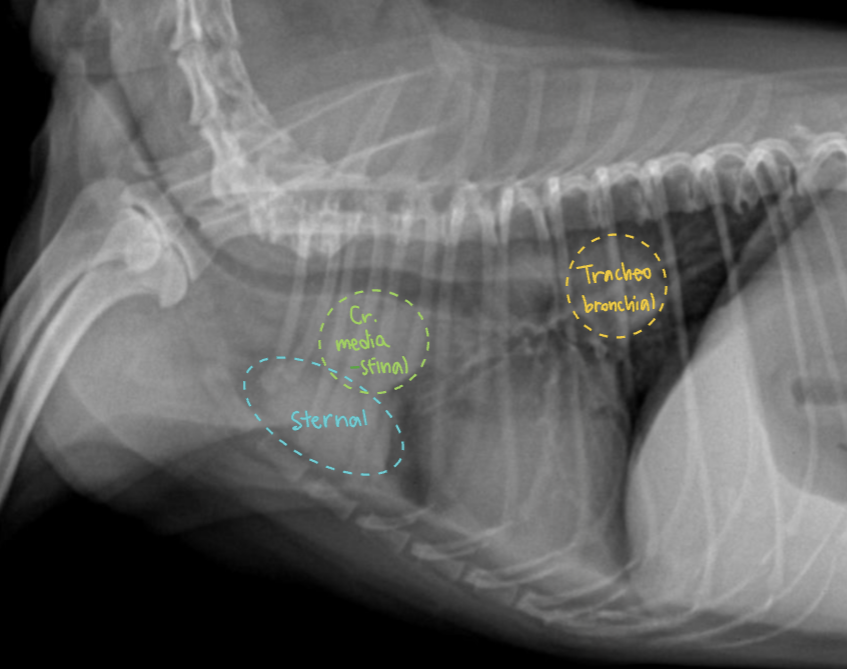

3. Mediastinal lymph nodes ๏ผˆ๋„์‹ํ™” ํ•„์š”๏ผ‰

(์…‹ ๋‹ค ๋น„๋Œ€๋˜์–ด ์žˆ์Œ)

• Cranial mediastinal LN (์ „์ข…๊ฒฉ ๋ฆผํ”„์ ˆ)

• Sternal LN (ํ‰๊ณจ ๋ฆผํ”„์ ˆ) : 2๋ฒˆ์งธ sternum ๋“ฑ์ชฝ, 1๊ฐœ ๋˜๋Š” ์—ฌ๋Ÿฌ๊ฐœ

• Tracheobronchial LN (๊ธฐ๊ด€๊ธฐ๊ด€์ง€ ๋ฆผํ”„์ ˆ) : carina ๊ทผ์ฒ˜ 2-3๊ฐœ, ์ธ์ ‘ํ•œ trachea ์••๋ฐ•ํ•  ์ˆ˜ ์žˆ์Œ

• Cr. mediastinal, Tracheobronchial : ํ‰๊ฐ• ๋ฌธ์ œ ์žˆ์„ ๋•Œ ๋น„๋Œ€

• Sternal : ๋ณต๊ฐ• ๋ฌธ์ œ ์žˆ์„ ๋•Œ ๋น„๋Œ€